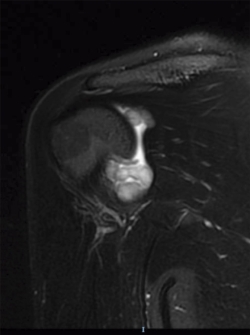

Se realizaron radiografías anteroposterior y axial de hombro, objetivándose calcificaciones intraarticulares, redondeadas, bien delimitadas. Ante dichos hallazgos, se procedió a la realización de una resonancia magnética (RM). En dicha prueba se objetivaron lesiones quísticas múltiples, bien delimitadas, algunas de ellas isointensas en T1, junto a otras lesiones hipointensas en T1 y T2 en la articulación glenohumeral compatibles con el diagnóstico de condromatosis sinovial (Figuras 1 y 2).

Figura 2. Resonancia magnética, T2 corte coronal: condromatosis sinovial.